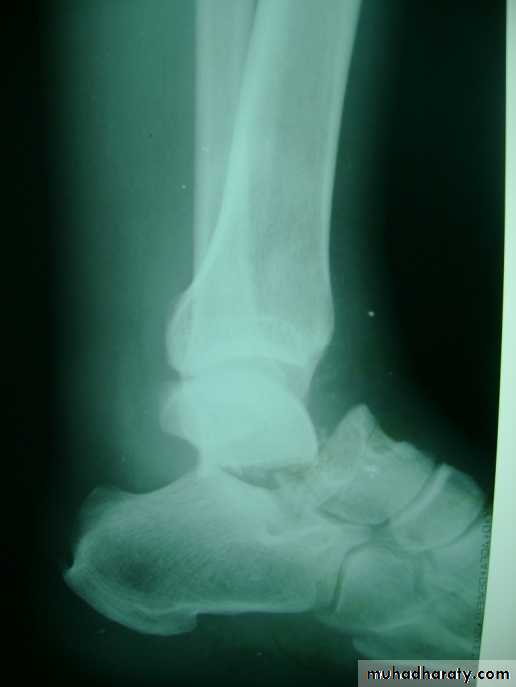

Fracture calcaneum

Fracture calcaneum and associated wedge fracture body of the vertebra

X- ray in lateral and axial view may shows chip, split, or crush fractures, CT sometimes used to assess the fracture details.